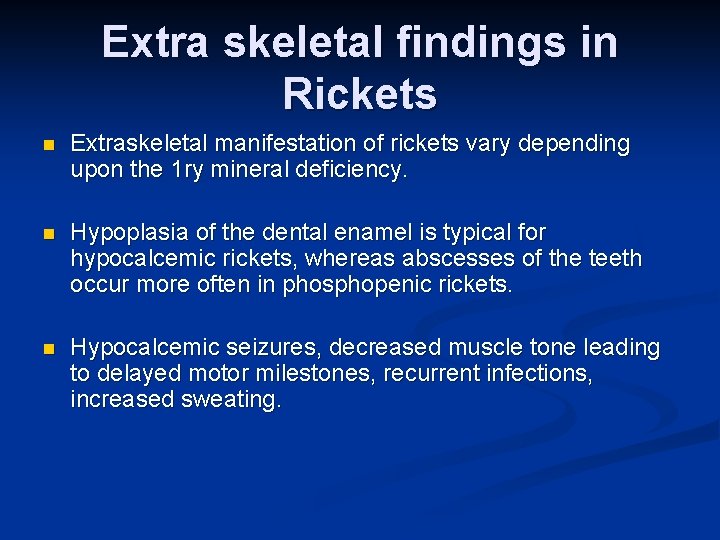

Extra skeletal findings in Rickets n Extraskeletal manifestation of rickets vary depending upon the 1 ry mineral deficiency. n Hypoplasia of the dental enamel is typical for hypocalcemic rickets, whereas abscesses of the teeth occur more often in phosphopenic rickets. n Hypocalcemic seizures, decreased muscle tone leading to delayed motor milestones, recurrent infections, increased sweating.